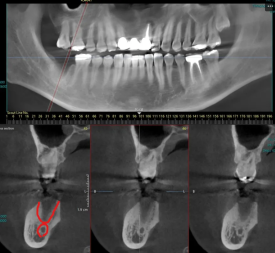

24.04.12 / 발치 후 약 1개월 경과 시점

상실된 어금니는 여건이 가능하다면 발치와 동시에 수술을 진행해서 회복 기간을 단축하고 있지만, 불가능한 때도 있는데 그중 하나가 치조골 잔존량이 적고 신경.관과 가까운 경우입니다.

요즘은 과거에 비해 짧은 임플란트(길이 4~5mm)여도 장기적으로 잘 고정되지만, 초기에 임플란트 고정력을 얻기 위해서는 신경.관 위로 최소 3~4mm 잇몸뼈의 두께가 확보되어야 하는데요.

사진 설명을 입력하세요.

환자분께는 CT 판독 사진을 보여드리고 충분히 상담해 드린 후 기간이 걸리더라도 안전하게 식립하기로 하였습니다.

- 하치조신경관 상방으로 3~4mm 잇몸뼈 두께 확보

- 치조골 염증 제거 후 충분한 회복 후 식립

- 3차원 CT로 위치 확인 후 식립